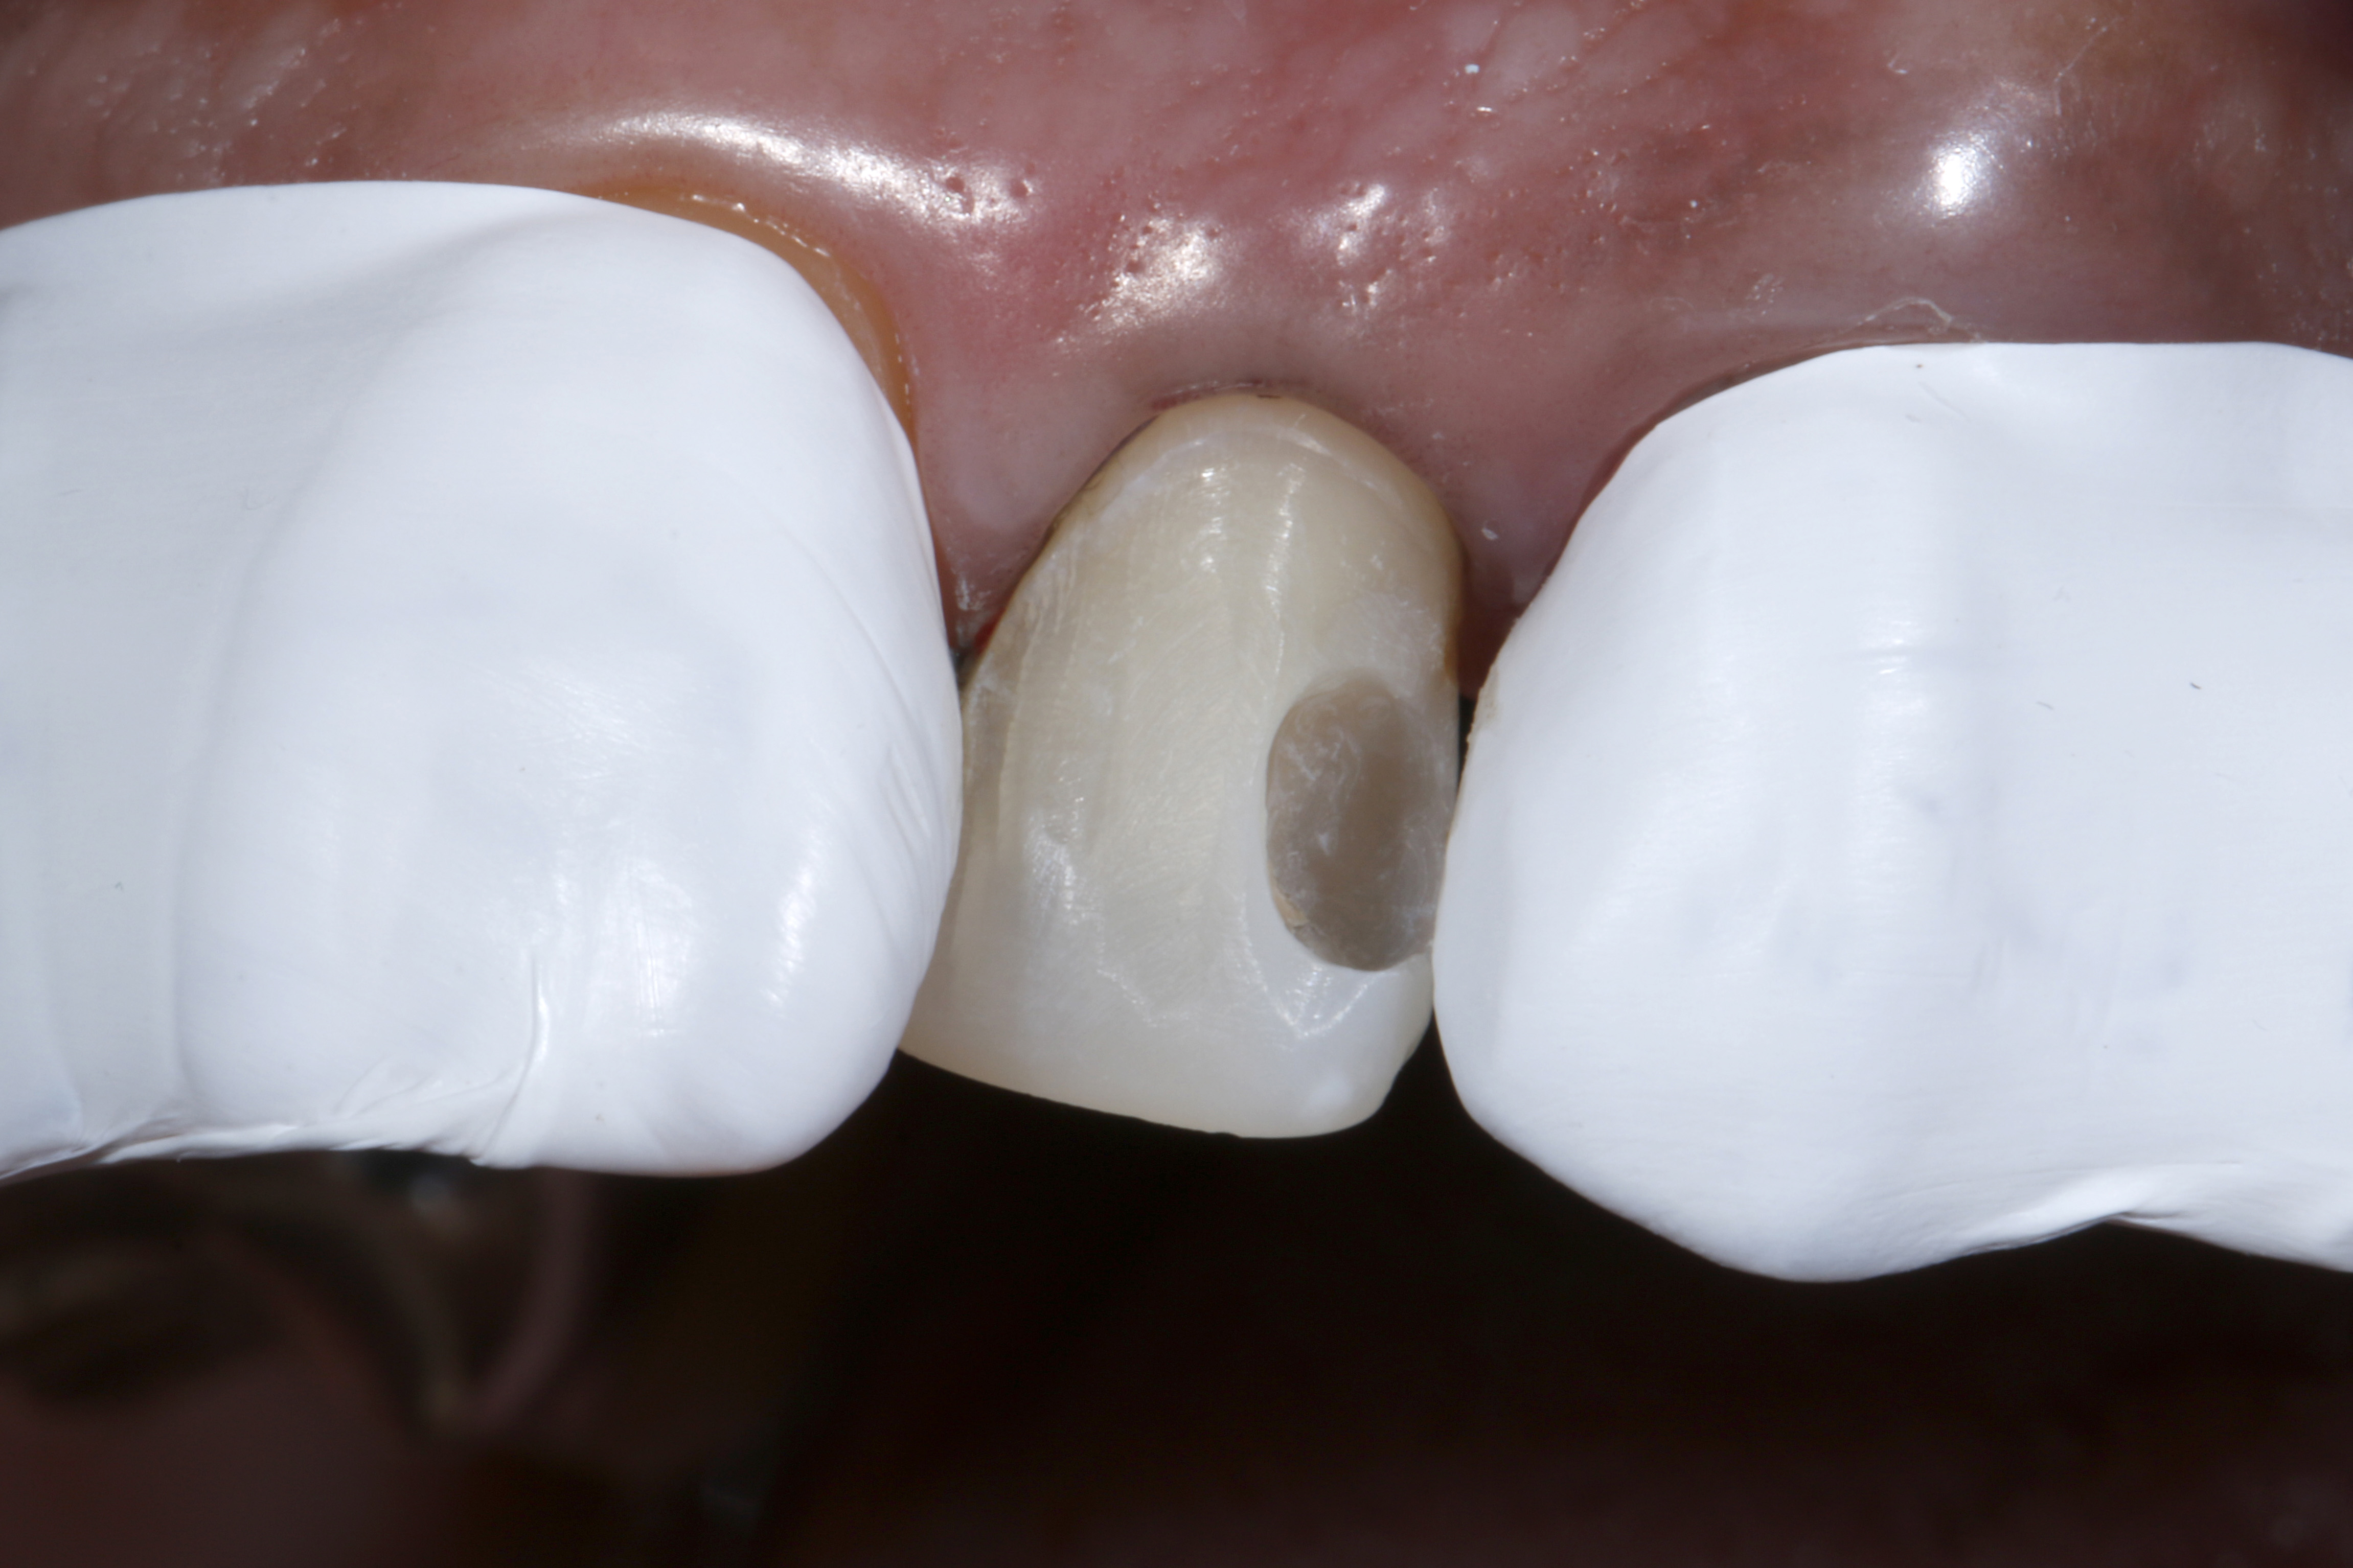

Leczenie rozpoczęto od dokładnego oczyszczenia zęba z zewnętrznych osadów za pomocą pasty profilaktycznej bez fluoru i gumki w kształcie kielicha. Następnie odpowiedni odcień kompozytu określono na wciąż wilgotnym zębie (ryc. 3).

Ryc. 3. Dobór odcienia na wilgotnym zębie

Wybrany odcień kompozytu sprawdzono, nakładając niewielką porcję kompozytu na powierzchnię zęba, który nie został wysuszony i nie był wstępnie zabezpieczony materiałem wiążącym (17). Konieczna jest polimeryzacja próbki kompozytu światłem przez czas określony przez producenta w celu uzyskania miarodajnego porównania optycznego. Dopiero przy wystarczającej ekspozycji na światło fotoinicjator kamforochinon, który jest zawarty w większości kompozytów i ma intensywnie żółty kolor, ulega w dużej mierze zużyciu i przekształceniu w bezbarwny produkt reakcji („fotowybielacz”) (18–23). Po polimeryzacji próbki kompozytu nałożonej na powierzchnię zęba, jej właściwości optyczne porównano z otaczającą zęba substancją pod względem odcienia i stopnia przezierności. Na tym etapie można łatwo dokonać korekty, zastępując niedopasowaną optycznie próbkę materiałem kompozytowym o zoptymalizowanym odcieniu. Ten indywidualny proces weryfikacji, który zajmuje bardzo mało czasu, gwarantuje, że do kolejnej odbudowy zostanie użyty optymalnie dopasowany materiał kompozytowy. Oznacza to, że w niemal wszystkich przypadkach można uniknąć czasochłonnych poprawek, a nawet nowych wypełnień z powodu skarg pacjentów na estetykę.

Ryc. 4. Usunięcie starego, dystalnego wypełnienia kompozytowego i niewielka preparacja powierzchni wargowej pod bezpośrednią licówkę kompozytową.